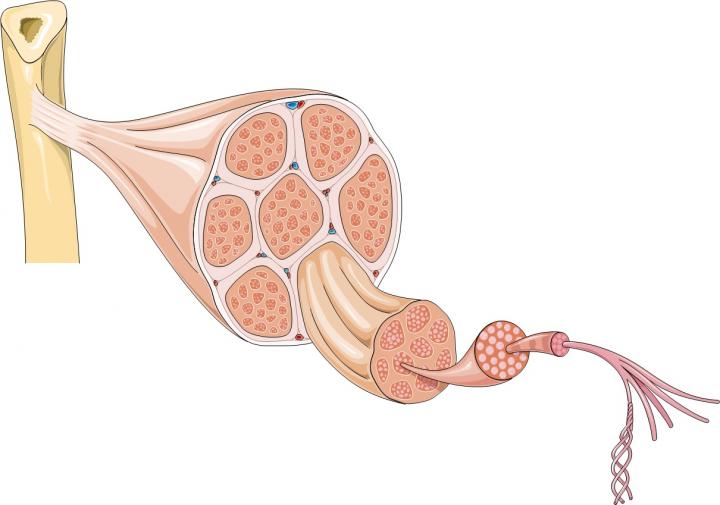

肌肉的大部分由肌纖維束形成,長(zhǎng)細(xì)胞含有許多細(xì)胞核;但肌肉也含有許多其他類型的細(xì)胞,包括干細(xì)胞。干細(xì)胞是人體內(nèi)置修復(fù)系統(tǒng)的一部分。它們可以產(chǎn)生祖細(xì)胞,也可以復(fù)制自己。骨骼肌含有一種稱為衛(wèi)星細(xì)胞的干細(xì)胞。當(dāng)肌肉纖維受損時(shí),它們會(huì)向衛(wèi)星細(xì)胞發(fā)送化學(xué)信號(hào),告訴它們形成新的肌肉纖維或與現(xiàn)有纖維融合以修復(fù)損傷。同時(shí),一些衛(wèi)星細(xì)胞會(huì)自我復(fù)制,以確保有足夠的干細(xì)胞可用于在未來(lái)繼續(xù)修復(fù)和更換肌肉纖維。

Emma Kemp 使用Servier Medical Art制作的肌肉結(jié)構(gòu)主圖和說(shuō)明 iPS 細(xì)胞在肌營(yíng)養(yǎng)不良癥細(xì)胞療法研究中的應(yīng)用?。Edwin P. Ewing, Jr 博士拍攝的杜氏肌營(yíng)養(yǎng)不良癥患者的肌肉圖像,由美國(guó)衛(wèi)生與公眾服務(wù)部公共衛(wèi)生圖像庫(kù)提供?。Mike Kayser的肌纖維照片?,Wellcome Images。?